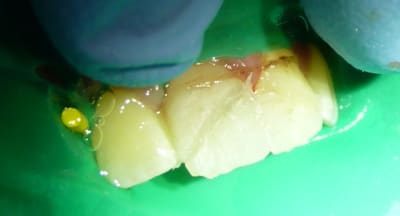

Patiente revue :

J'ai tenu compte de tes conseils Céramik : j'ai juste fait un collage, sans interposer de matériau.

Je n'ai fait un biseau qu'en vestibulaire : j'aurai du biseauter en palatin aussi pour augmenter la surface de collage.

La patiente est en classe II, ses incisives n'assurent aucun guidage.

J'ai encore beaucoup de mal à faire des compos sur incisives centrales... Le résultat est assez moche, je manque d'expérience.

La patiente et sa maman sont ravies. Je leur ai expliqué que c'était une indication de facettes.

Non, le résultat est pas mal, c'est plus en per-op que ta digue n'est pas optimale (mise comme ça, elle était plus embêtante qu'autre chose, non?). C'est moi ou tu n'as pas mis de crampons?

Ou de compos directs stratifiés. Ou encore une tout céram sur la 11.

Il est fort probable que tu aies à réaliser l'endo de la 11, à moins que des pros nous disent que c'est rattrapable avec du MTA ou autre